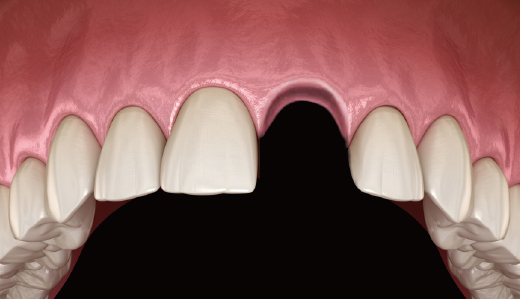

1. 술전